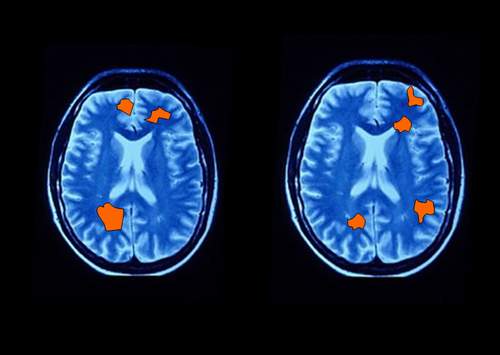

ولكن باحثين من جامعة كاليفورنيا وجدوا أن دماغ المرأة يتصرف بشكل مختلف عن دماغ الرجل حتى في حالة الراحة أو السكون!! أي عندما يكون الرجل جالساً لا يعمل أي شيء، ولا يفكر بشيء، وكذلك عندما تكون المرأة جالسة لا تفكر بشيء فإن التصوير بالرنين المغنطيسي أظهر أن النشاط في مناطق الدماغ للرجل يختلف عن دماغ المرأة بشكل واضح.

فقد كشف الدكتور Larry Cahill أن دماغ الرجل يعالج المعلومات بطريقة مختلفة جداً عن دماغ المرأة، حتى في حالة الراحة، واستخدم الباحث إشعاع Positron Emission Tomography أو اختصاراً PET في تجربة تشمل 36 رجلاً و 36 امرأة، وذلك لدراسة نشاط الدماغ أثناء الراحة دون التفكير بشيء، وأظهرت الصور أن المناطق التي تنشط في دماغ المرأة تختلف عن المناطق التي تنشط في دماغ الرجل!

تظهر الصور الناتجة عن جهاز المسح بالرنين المغنطيسي الوظيفي fMRI أن الرجل والمرأة عندما يقومان بنفس العمل فإن مناطق مختلفة من الدماغ تنشط، بما يؤكد بوضوح كامل أن طريقة عمل الدماغ لدى الرجل تختلف عن طريقة عمل الدماغ لدى المرأة.

هناك بحث جديد أظهر أن الرجل والمرأة عندما يقومان بنفس العمل فإن المناطق التي تنشط في الدماغ تختلف بين المرأة والرجل، والعجيب أن الرجل والمرأة عندما يقومان بأعمال مختلفة فقد تنشط المنطقة ذاتها من الدماغ، وهكذا نجد الاختلاف يتجلى في كل شيء بين الذكر والأنثى.